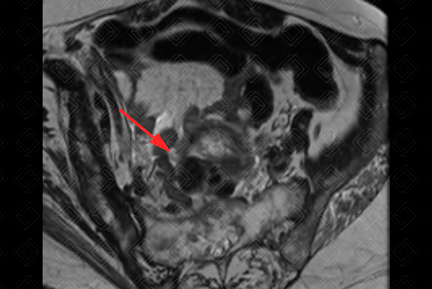

Descrição das figuras 1, 2, 3 e 4: Ressonância magnética da pelve feminina. Imagens pesadas em T2 nos planos axial e sagital (A = bexiga; B = útero; C = reto). Útero em retroversão, de contorno lobulado e sinal heterogêneo, por conta de nódulos miometriais, bem delimitados, hipointensos em T2, compatíveis com leiomiomas, destacando-se:

• Transmural, corporal posterior, medindo 5,0 x 4,8 x 4,6 cm (setas vermelhas à direita);

• Subseroso, corporal lateral direito, medindo 3,0 x 2,0 x 1,8 cm (setas vermelhas à esquerda).